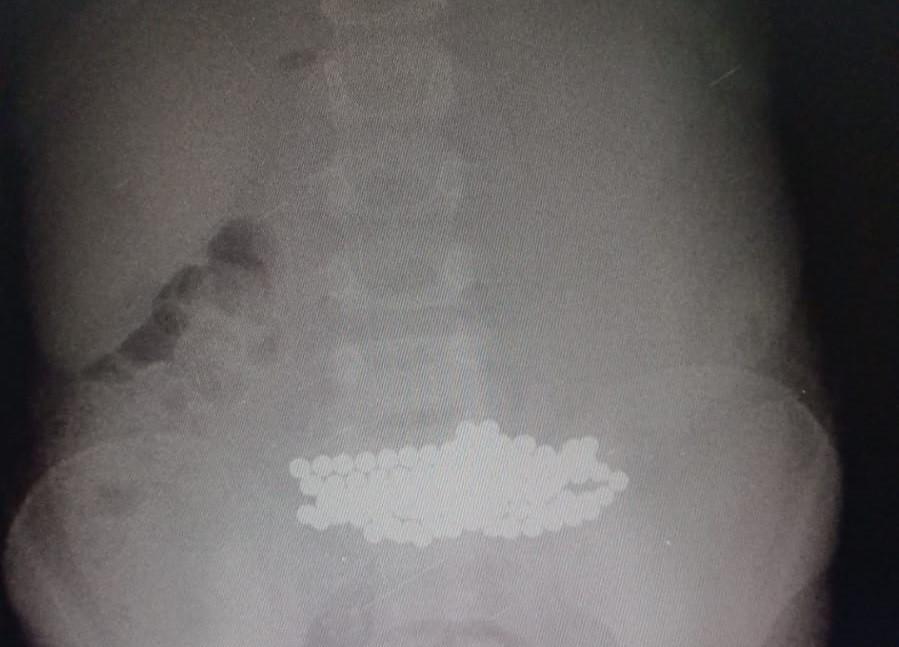

Сложную операцию провели семилетней девочке в Нур-Султане. Из ее организма извлекли более ста мелких магнитов, передает Liter.kz со ссылкой на сайт акимата города.

«На прошлой неделе провели операцию 7-летней девочке. У ребенка обнаружили забитый инородными телами нос уже с перфорацией перегородки. После выявили огромное скопление магнитов в желудке. В итоге мы вытащили более 100 мелких магнитов», - рассказал руководитель хирургического блока многопрофильной городской детской больницы №2 Ринат Байгиреев.

Фото: astana.gov.kz